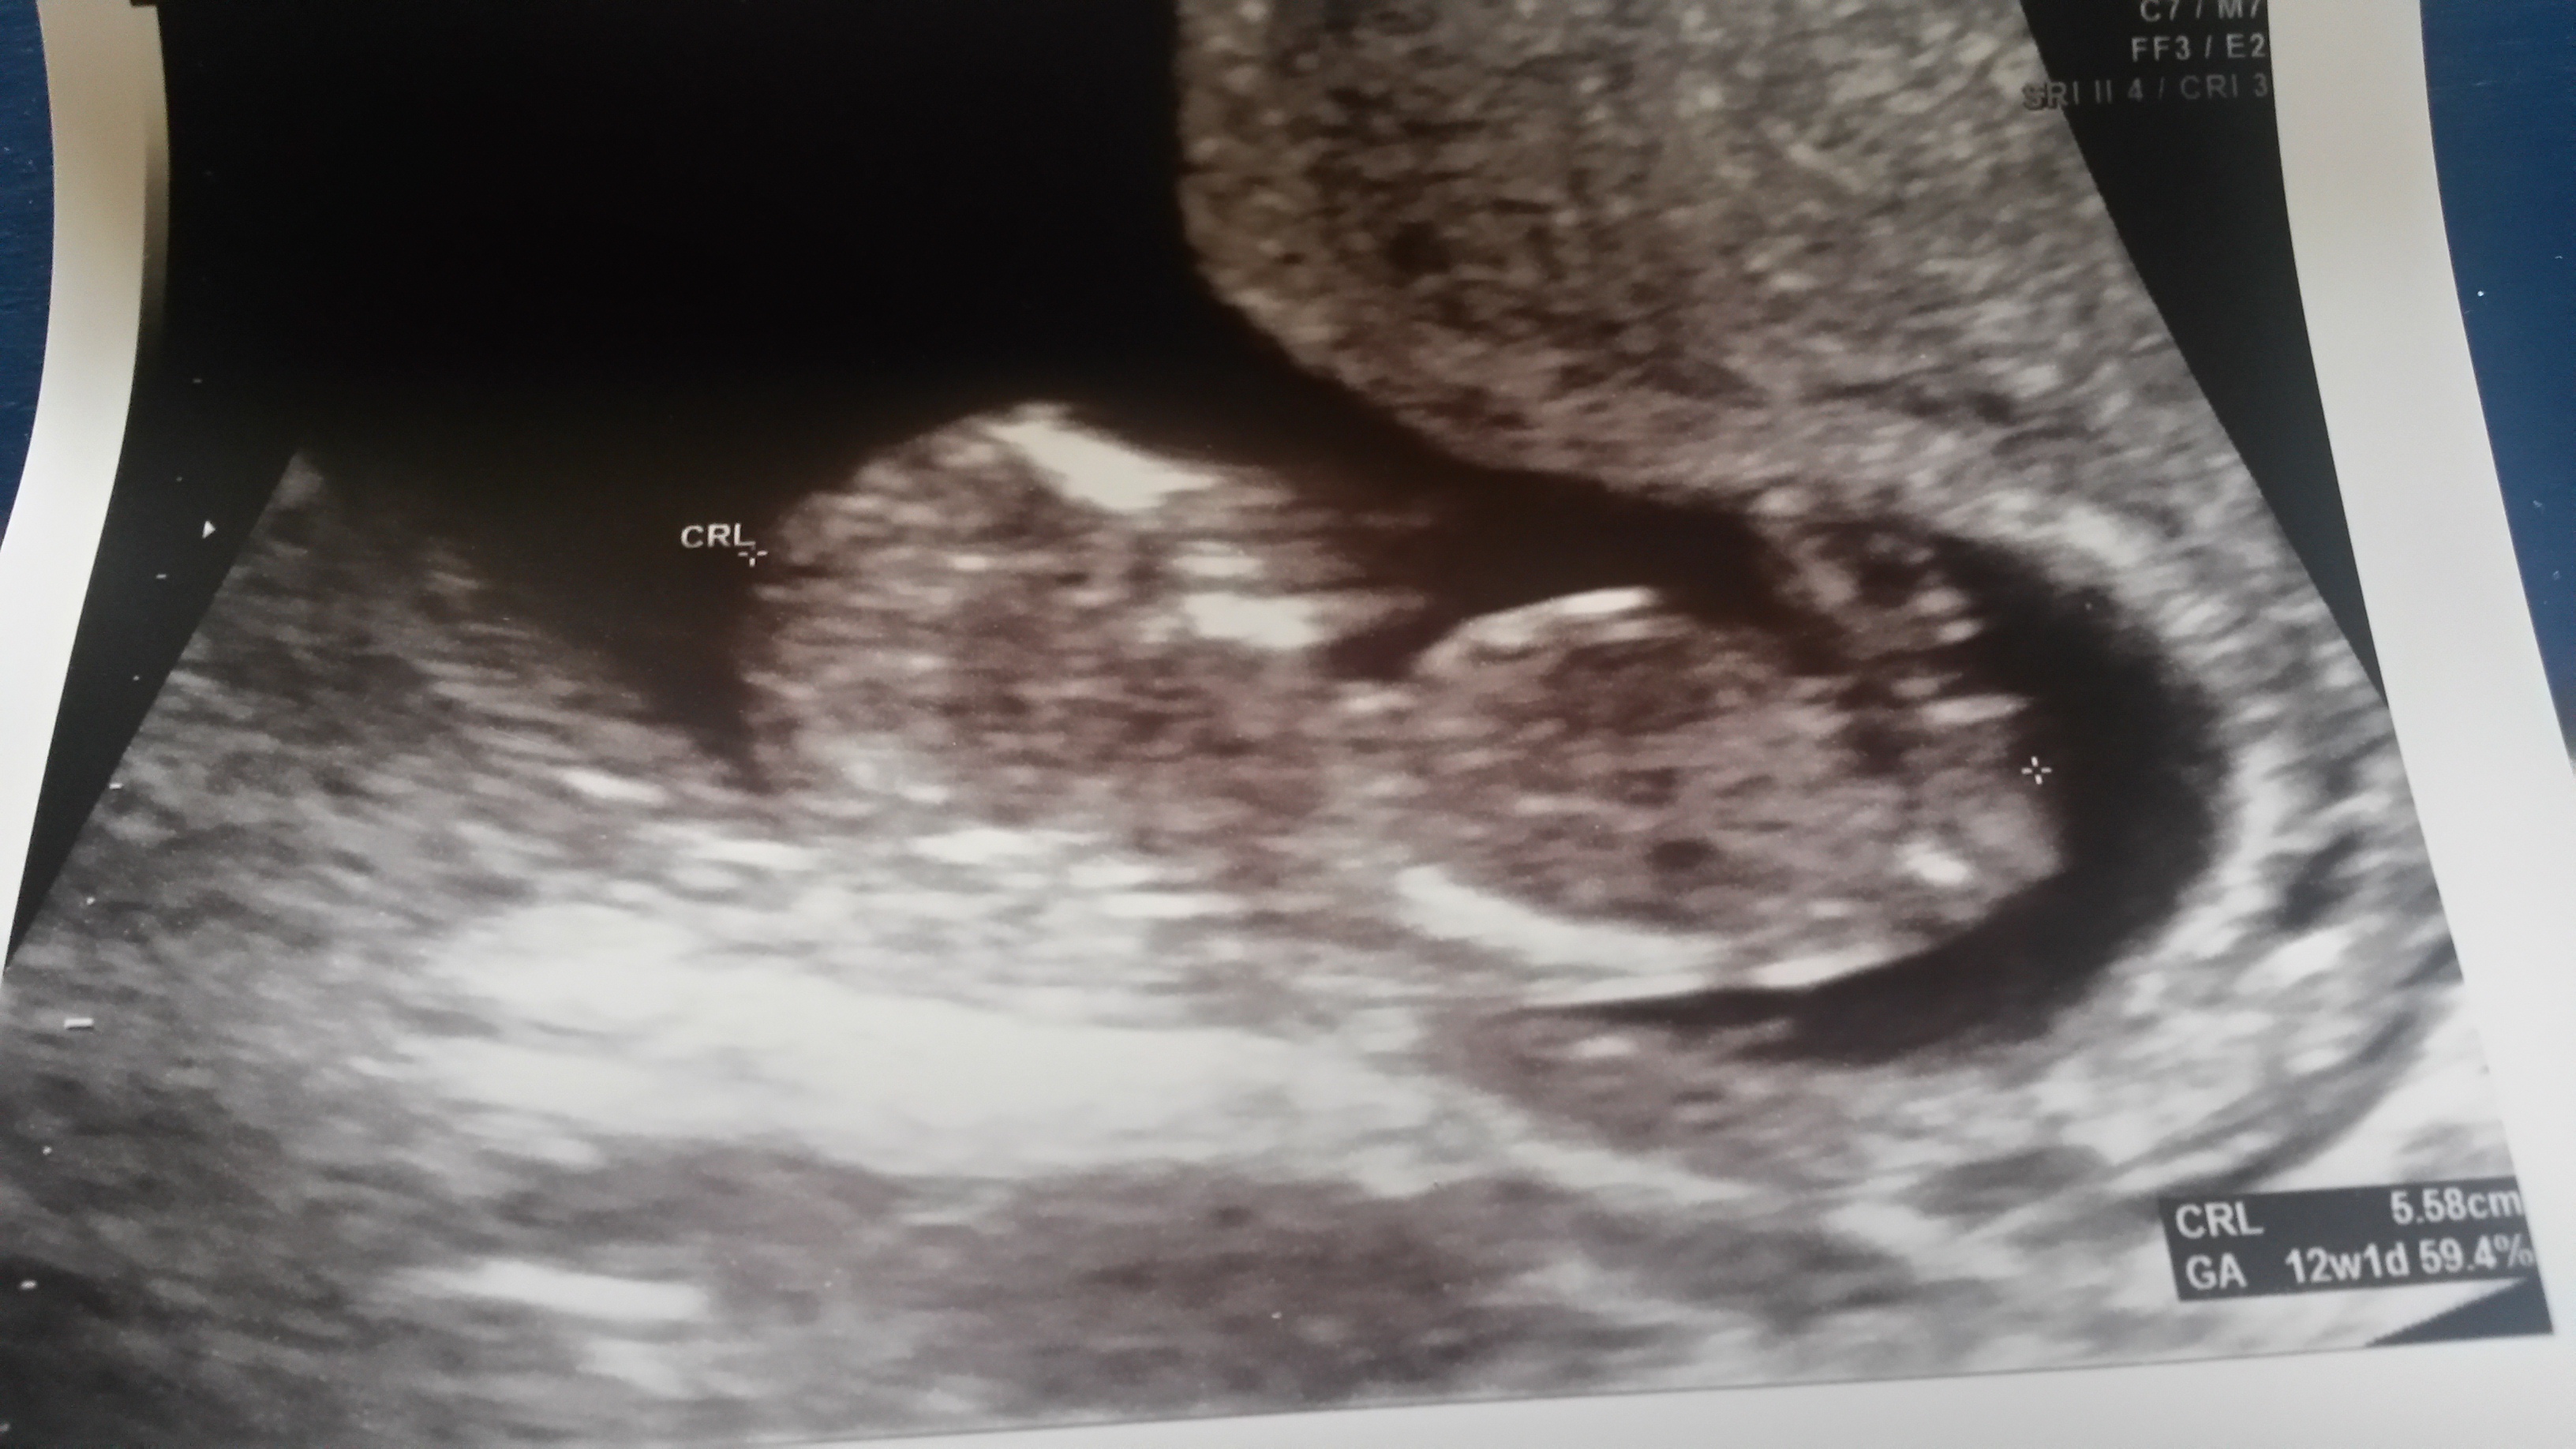

I already knew we were having a boy from the MaterniT21 blood test but we could clearly see the penis on today's ultrasound (12 weeks 3 days).

I'm high risk and have quick ultrasounds with every OB visit.

Anyway, the point of my post is that if any of you have a 12 week ultrasound coming up, and it's a boy, you may be able to see!

(Obviously quality of US machine, baby's position, uterine positioning, etc all come into play.)

But, It's on both boys AND girls. So if anyone sees a small appendage protruding, it's not necessarily a boy...

I guarantee what you saw was this "nub".

There IS a "nub theory" some techs swear by. Depending on the angle of the nub (above 30 degrees means boy, I think) you can sometimes determine the gender but obviously it's not 100% accurate